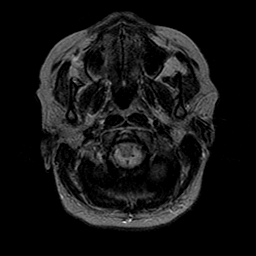

Cerebral hemorrhage, MR Study mr-t2 -- Slice #2

[Home][Help][Clinical] Slice 2